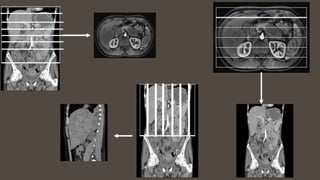

A plane passes through the

anatomical position.

It’s like slicing a loaf of bread. Instead of looking at the

or planes?

CORONAL

SAGITTAL

OBLIQUE

AXIAL

(TRANSVERSE)

plane

divides the

body into

right and

left

portions.

This is a

vertical

plane divides

the body into

front and

back or

anterior and

posterior

plane.

Axial plane

superior

and inferior

horizontal